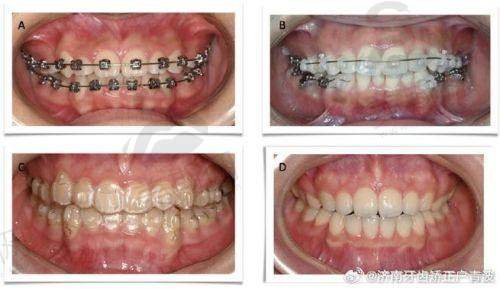

2. 隐形正畸中 心:提供隐适美、时代天使、正雅等全品牌隐形矫治服务,通过口扫数据建模,实现矫正周期缩短20%。

在隐形正畸技术方面,医院实现全流程数字化管理:使用3Shape TRIOS口扫仪3分钟完成牙列扫描,数据实时传输至正畸设计系统,医生可与患者共同调整方案。其特色"双膜矫正技术",通过动态追踪牙移动轨迹,每阶段制作2副矫治器,使牙齿移动精度提升30%。临床数据显示,采用该技术的患者中,83%提前1 - 3个月完成矫正目标,覆合覆盖改善度达92%。